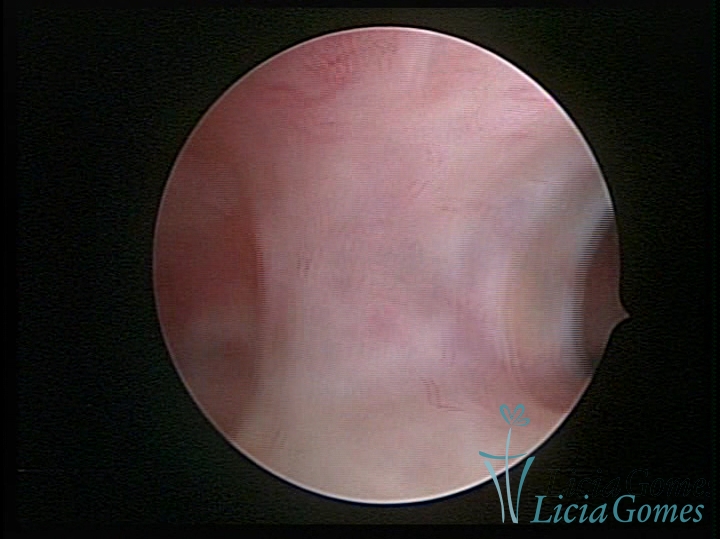

FIBROUS SYNECHIA

Uterine synechiae are scars (adherence) between the surface of the uterine walls, which may occur after the surgical procedure, uterine curettage, or after an inflammatory process in the uterine cavity (endometritis), which may lead to menstrual changes, infertility and obstetric complication such as abortion and premature birth.